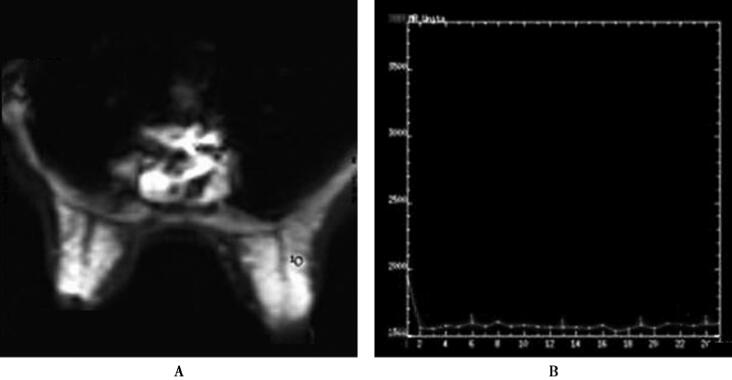

图1(右乳)导管内乳头状瘤

A.T2*WI首次通过灌注图像病灶未见明显灌注;B.灌注时间信号强度曲线呈趋于平台型曲线,未见明显信号丢失;C、D.T1WI动态增强图像,病灶显著均匀强化,边缘较清晰;E.T1WI动态增强时间信号强度曲线表现为平台型(Ⅱ型)

乳腺导管内乳头状瘤因内部成分不同,在T1WI呈等信号、低信号或高信号,T2WI呈高信号或混杂信号,增强MRI表现为早期均匀或不均匀增强结节,动态增强曲线呈平台型或流出型,可伴导管扩张。

该病例鉴别诊断要考虑到乳腺纤维腺瘤,纤维腺瘤的边缘清晰光滑,TIC曲线多呈持续型或平台型,该病例TIC曲线呈平台型,需要与之鉴别诊断。由于该病例的鉴别诊断困难,参考T2*WI首次通过灌注图像,结果病灶无明显灌注,时间-信号强度曲线趋近于平台型,未见信号丢失,这些改变符合良性病变特点,有利于鉴别诊断。